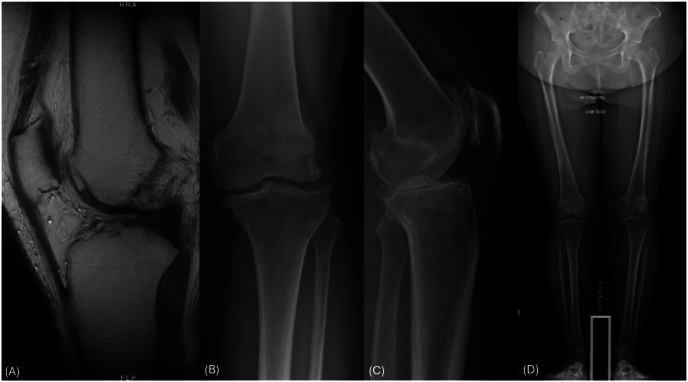

We present a case involving a 47-year-old patient with medial compartment osteoarthritis and complete ACL rupture. The patient underwent a simultaneous robotic-assisted UKA and ACLR using the CORI Surgical System (Smith&Nephew, London, UK). This approach enables accurate tibial tunnel placement and precise soft tissue balancing. The robotic system facilitates real-time gap assessment and balancing, reducing the risk of over- or under-constraint during ACL graft tensioning.

The procedure was performed with a standard medial parapatellar approach. Key steps included hamstring autograft harvesting, femoral and tibial tunnel creation, and robotic-assisted implant positioning. Post-operative rehabilitation allowed full weight-bearing by the third week.